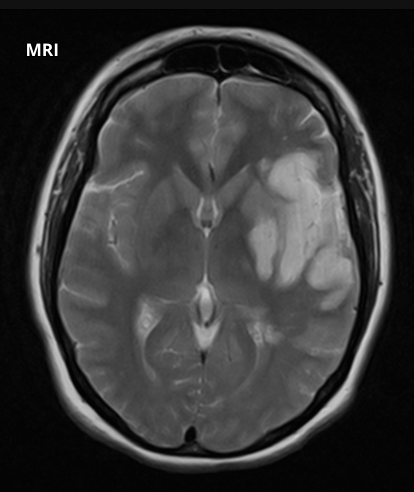

What does this image show?

Ischaemic stroke - There has been ischaemia and infarction of this patient’s left hemisphere.

This ischaemic stroke has been caused by blockage of what artery?

Left middle cerebral artery

What are the symptoms of an MCA ischaemic stroke?

Unilateral contralateral motor weakness

Sudden worsening or loss of senses

Dysarthria

Aphasia

Neglect

Ataxia